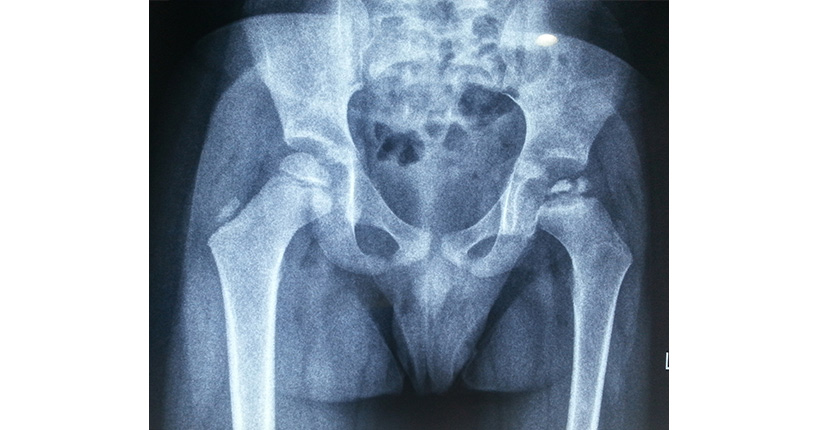

In this condition, children experience a brief blood supply loss to the rounded head of the thigh bone (femur), usually known as the ball part of the ball and socket joint. With inadequate blood supply, the bone becomes weak, leading to multiple small fracture lines in the head of the femur. Further, the bone gets reabsorbed and leads to the collapse of the femoral head and possible loss of its roundness.

The condition is not permanent as the blood supply returns eventually, and bones re-ossify. However, the femoral head may not retain a round shape due to the disease or re-ossification process if the femoral head slips out of the acetabulum (socket of ball and socket joint) before complete healing. As a result of this, children tend to develop early osteoarthritis of hip.

In case the disease is suspected, our team will conduct an X-ray of the child's hips. Next, we may recommend an MRI in a few cases. In some cases, we might ask for certain blood test reports to rule out infections and other medical conditions.